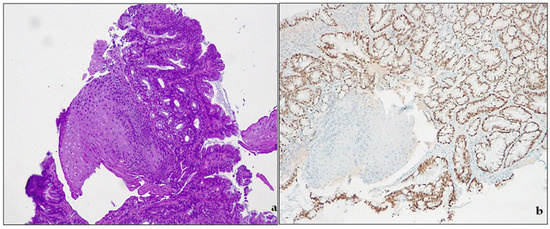

- Low-grade dysplasia—LGD. The cells in LGD display nuclear enlargement, elongation, hyperchromasia, and stratification, but their nuclear polarity is retained (Figure 4). Although the dysplastic crypts show minimal architectural changes, the lamina propria between them is still visible. The nuclei are slightly enlarged, and the number of goblet cells present may range from a few scattered ones to numerous.